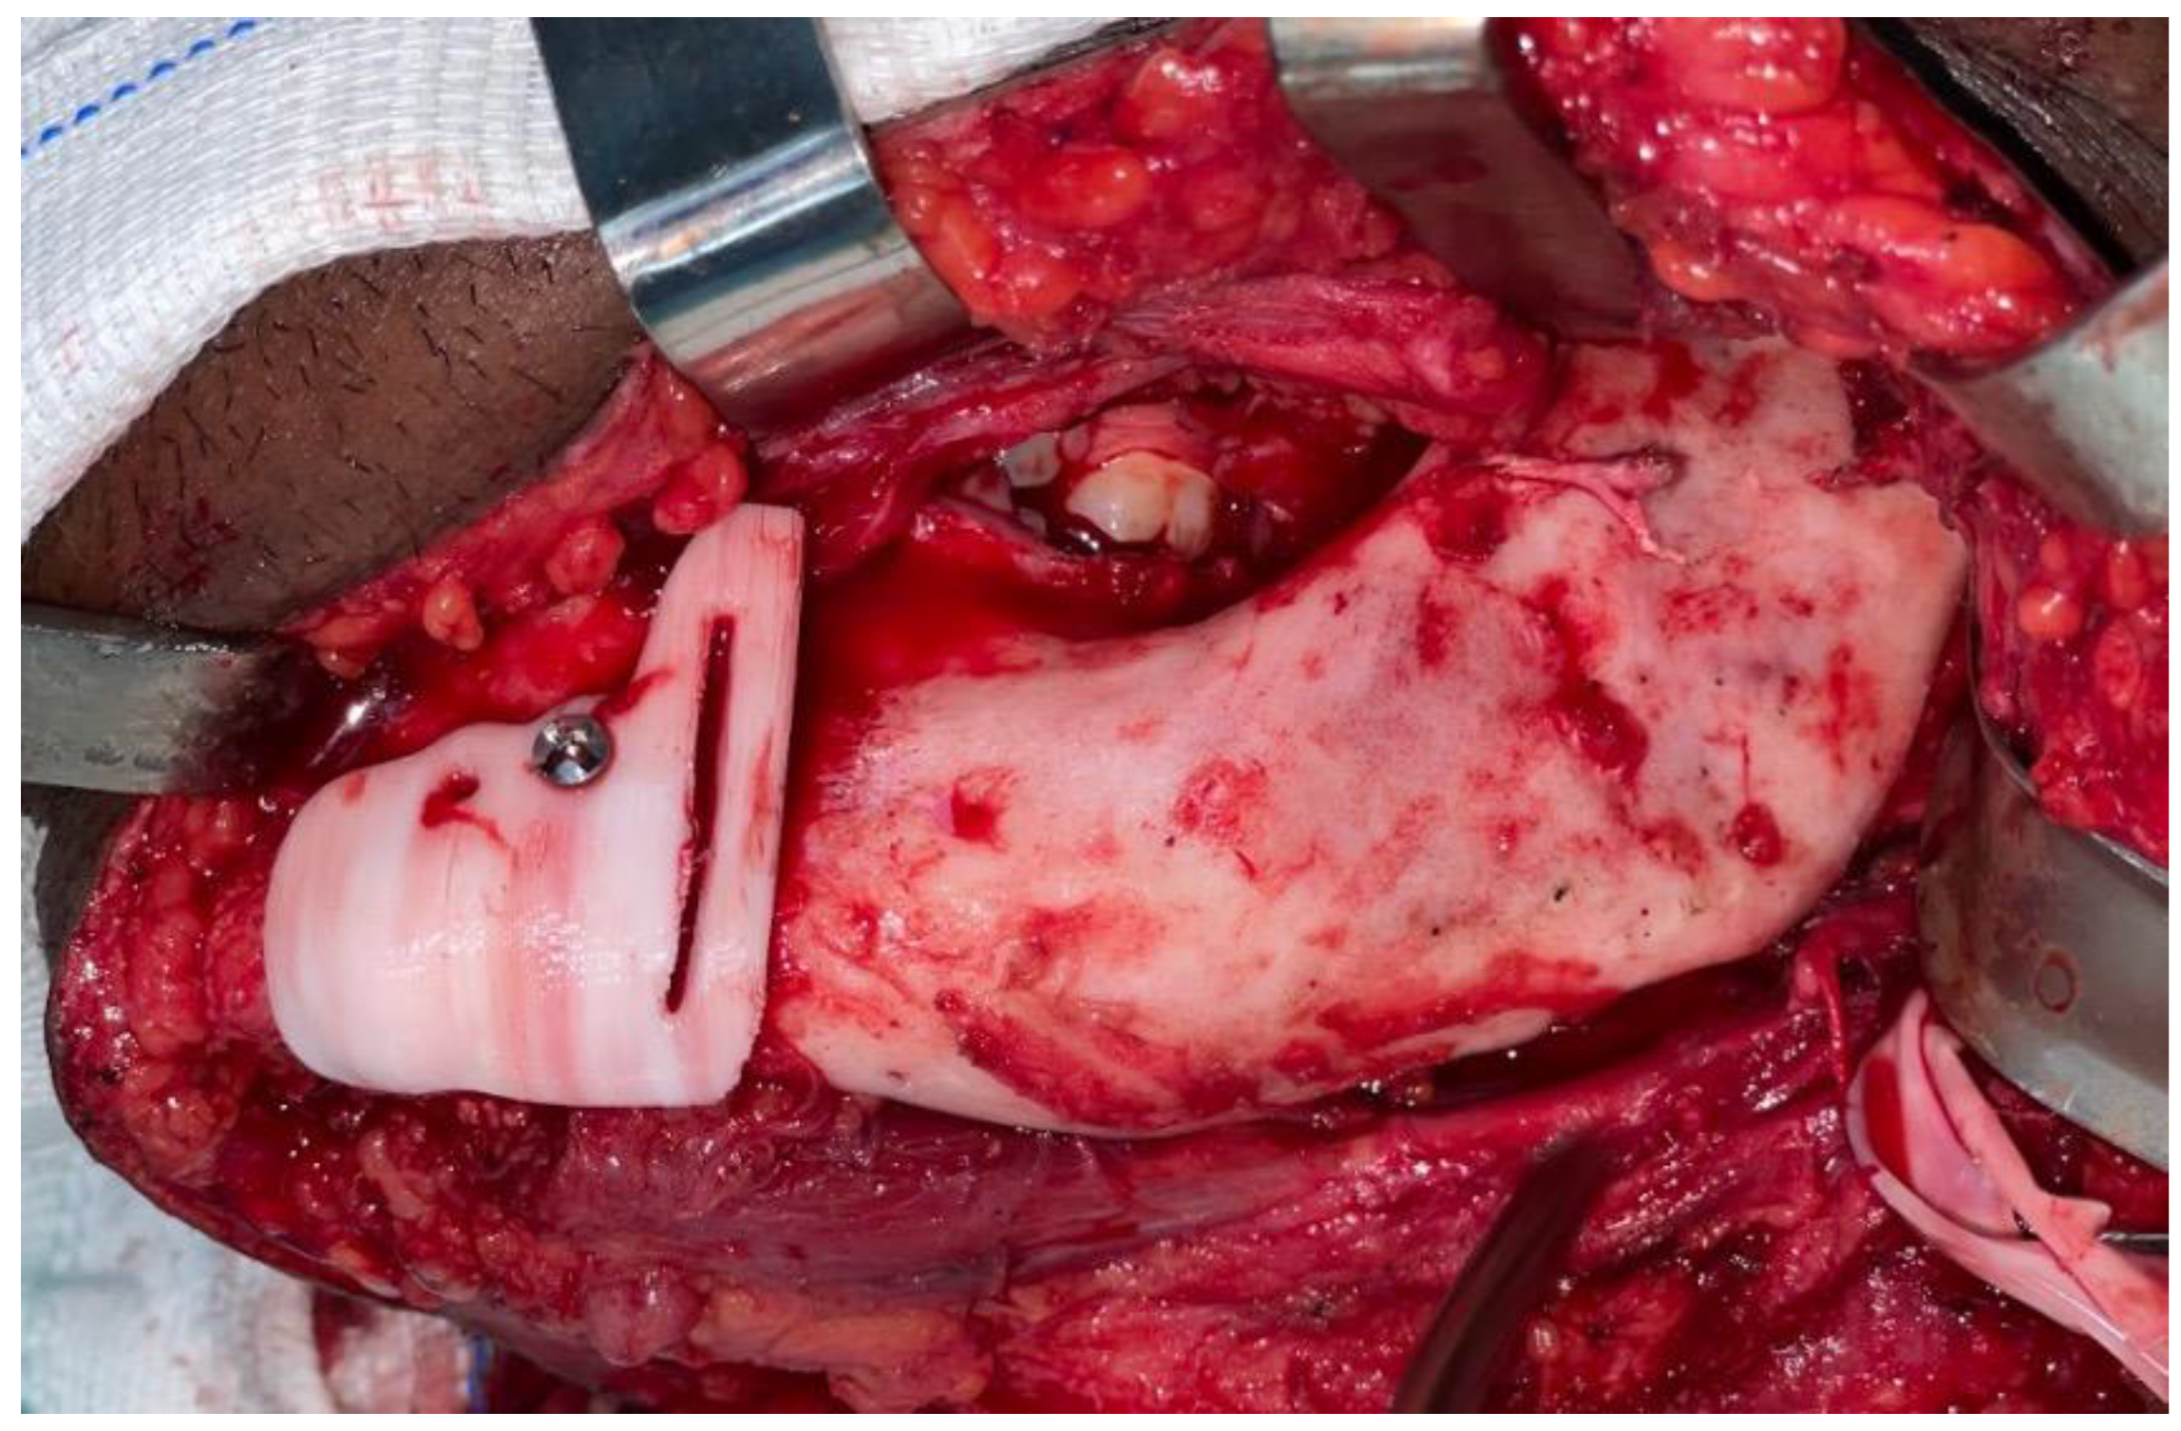

2.1. Case 1